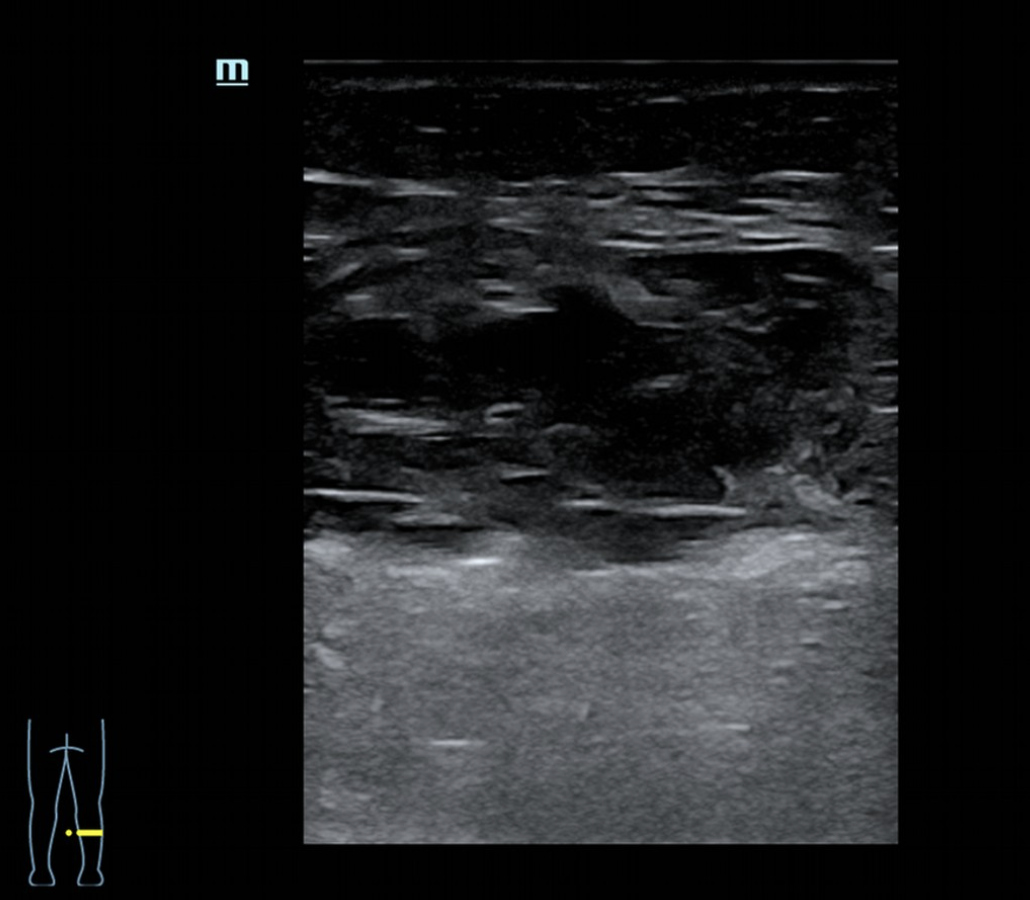

La ecografía, realizada con sonda de alta frecuencia sobre la cara medial e interna del gemelo, muestra una disrupción fibrilar con un defecto de 32,9 mm en su eje mayor y 8,3 mm en el menor. Se aprecia pérdida de la arquitectura normal con áreas hipo e hiperecogénicas compatibles con sangrado, edema y retracción de los extremos de la rotura. Se descarta TVP en eje poplíteo.

El diagnóstico final es rotura fibrilar del gemelo medial secundaria a sobreesfuerzo. La TVP constituye el principal diagnóstico diferencial en un cuadro de dolor agudo de pantorrilla con hematoma, especialmente en pacientes con antecedentes venosos relevantes.